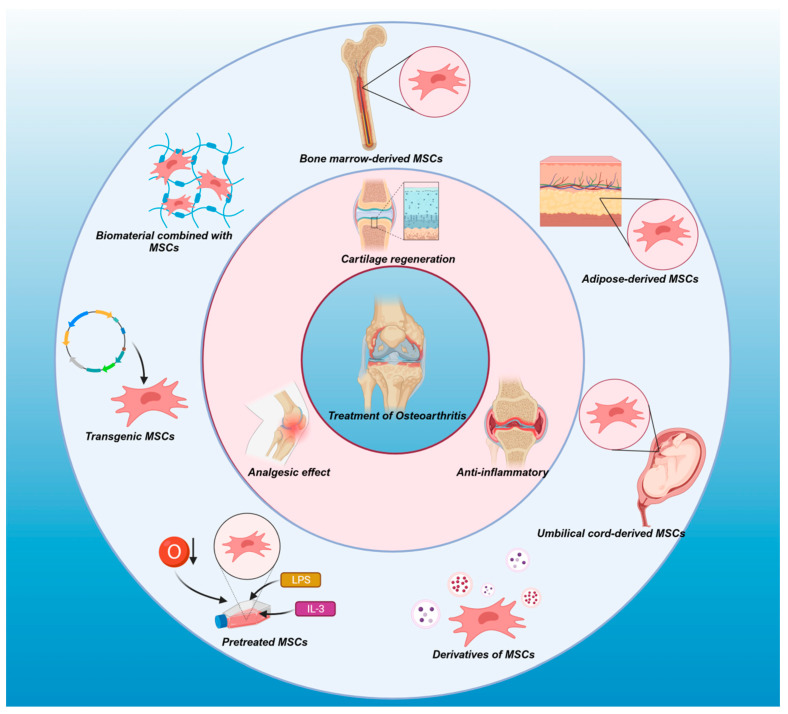

間充質(zhì)干細胞在治療自身免疫性疾病和組織/器官修復方面已表現(xiàn)出顯著的功效。在骨關節(jié)炎治療中,間充質(zhì)干細胞在幾個方面發(fā)揮著關鍵作用(圖1)。

圖1:不同來源的間充質(zhì)干細胞(MSC)——包括衍生物、預處理的間充質(zhì)干細胞和轉(zhuǎn)基因間充質(zhì)干細胞,以及與間充質(zhì)干細胞結合的生物材料——有助于軟骨再生、抗炎反應、免疫調(diào)節(jié)和鎮(zhèn)痛作用。這些多功能應用使 MSC 成為骨關節(jié)炎 (OA) 的潛在治療劑,為減緩 OA 的進展提供了前景。